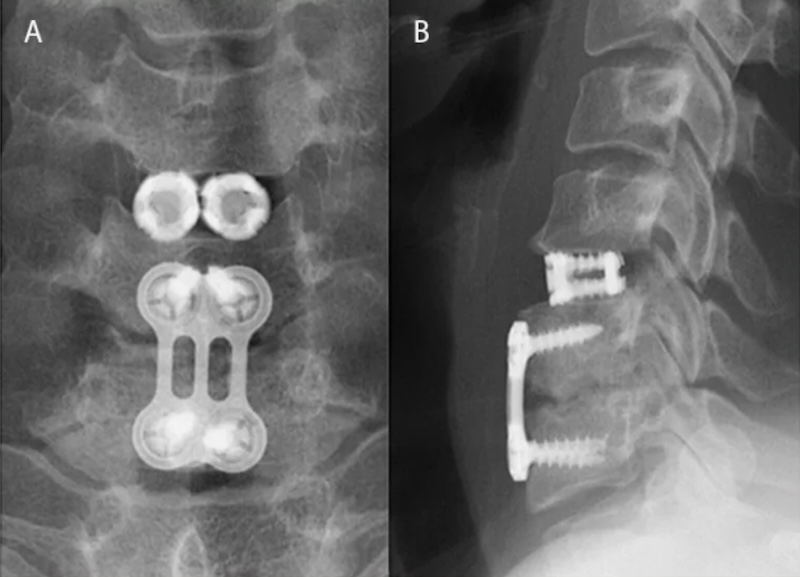

VariLift-C Cervical Stand-alone Expandable Threaded ACDF Spacer

Configuration: Cage Alone , 0-Profile (Integrated screws)

The VariLift-C is a Cervical Expandable Titanium spacer for use in the ACDF procedure and approved for use in the single level either with or without supplemental fixation and used singly or bilaterally. The cage has an external threads with large fenestrations for graft. The expansion plate expands the central core.